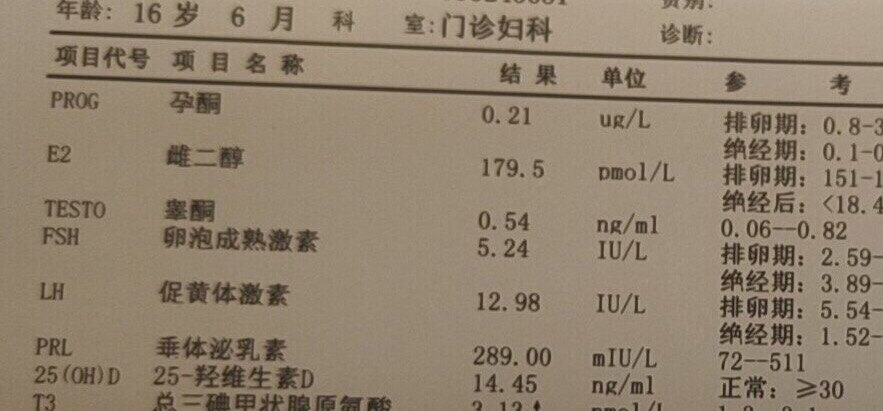

糖耐量受损和高同型半胱氨酸血症

胰岛素抵抗

维生素D缺乏

这是一位16岁的高中生,12岁初潮,月经不规律,这次是因为闭经四年前来就诊。根据她的病史症状、一系列化验和超声检查结果,我给她下的诊断是:糖耐量受损,胰岛素抵抗,高同型半胱氨酸血症,青春期多囊卵巢综合征。她的25羟基维生素D只有14.45ng/ml,所以我还诊断她维生素D缺乏。

这个才16岁的花季少女,她的同型半胱氨酸这么高(≧10μmol/L为高血同),估计她的动脉粥样硬化已经起步n年了。如果现在不开始加以控制的话,估计她在40岁左右就会出现心梗或脑梗。